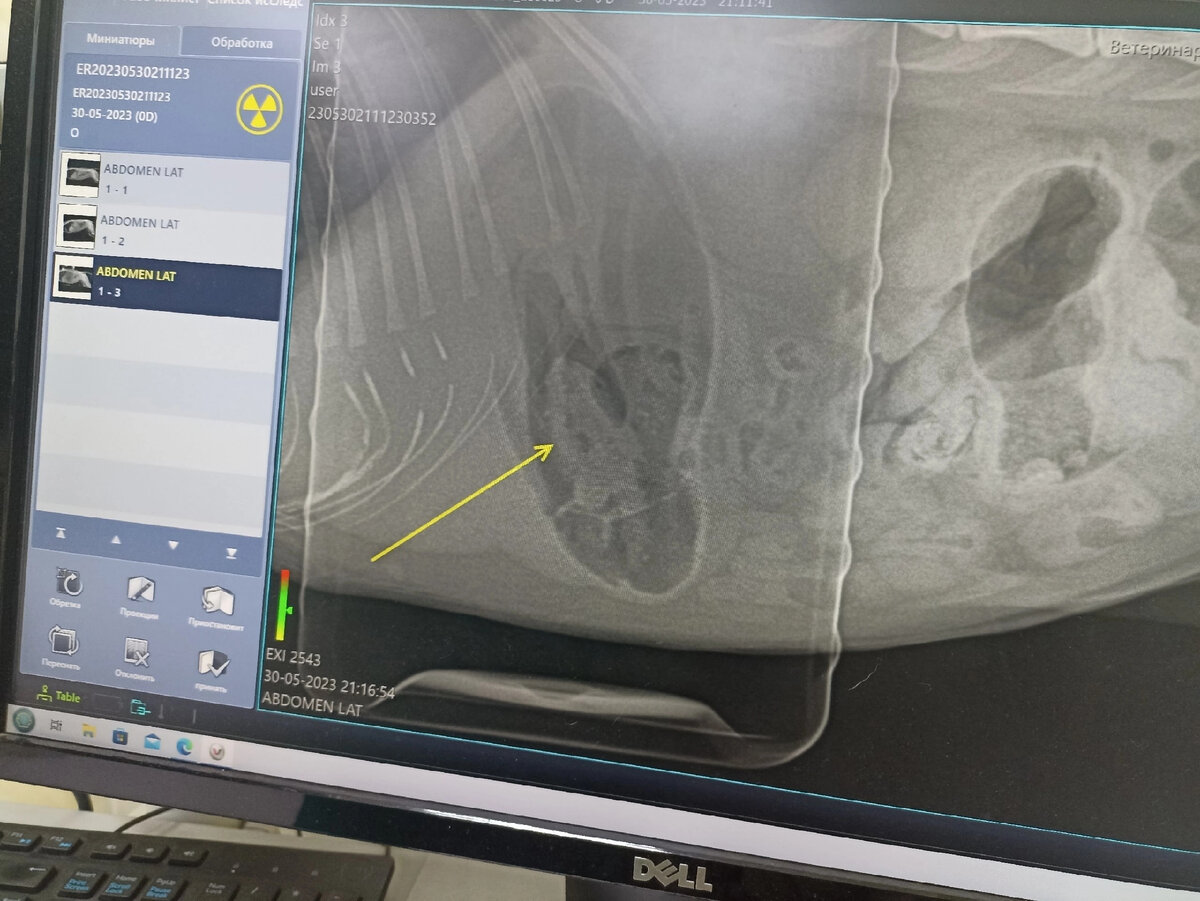

Вчера вечером, уже в 21 час, Василисе сделали рентген. Потому что кишки стоят, повторное УЗИ брюшной выявило, что -то в желудке... По рентгену, да что- то в желудке... Необходима диагностическая, лапаротомия.. По другому никак.

Риск конечно, но делать надо. Кошка не ест, у нее боли, атония кишечника...

Оперировать Василису не стали. Переделали рентген. Желудок чистый, значит ушло все в кишечник, может выкакает) чувствует она себя хорошо, повеселела, ест. Сегодня контрольное УЗИ и наверно поедем домой.